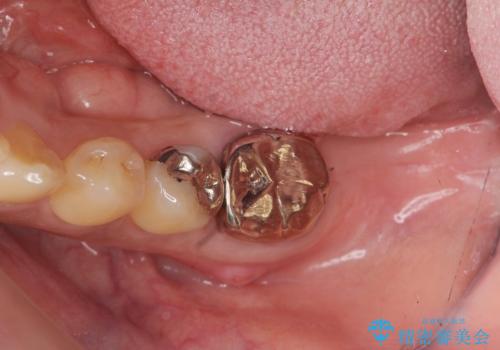

歯周病に対する全体治療

- 近医で「重度の歯周病です、入れ歯にする必要がある。」、と言われ入れ歯以外の方法がないか相談にみえられました。

再生治療、歯周外科を行うことで歯周病治療を行い、残すことのできる歯の歯周環境を整える。

残すことのできない歯は抜去したのち骨造成を含めたインプラント治療を行い、しっかりとした咬合関係を確立していきます。

治療期間はかかりましたが、しっかりと歯周病治療・インプラント治療を行ったおかげで歯周病の状態は非常に良くなり、安定した咬合関係を確立することができました。